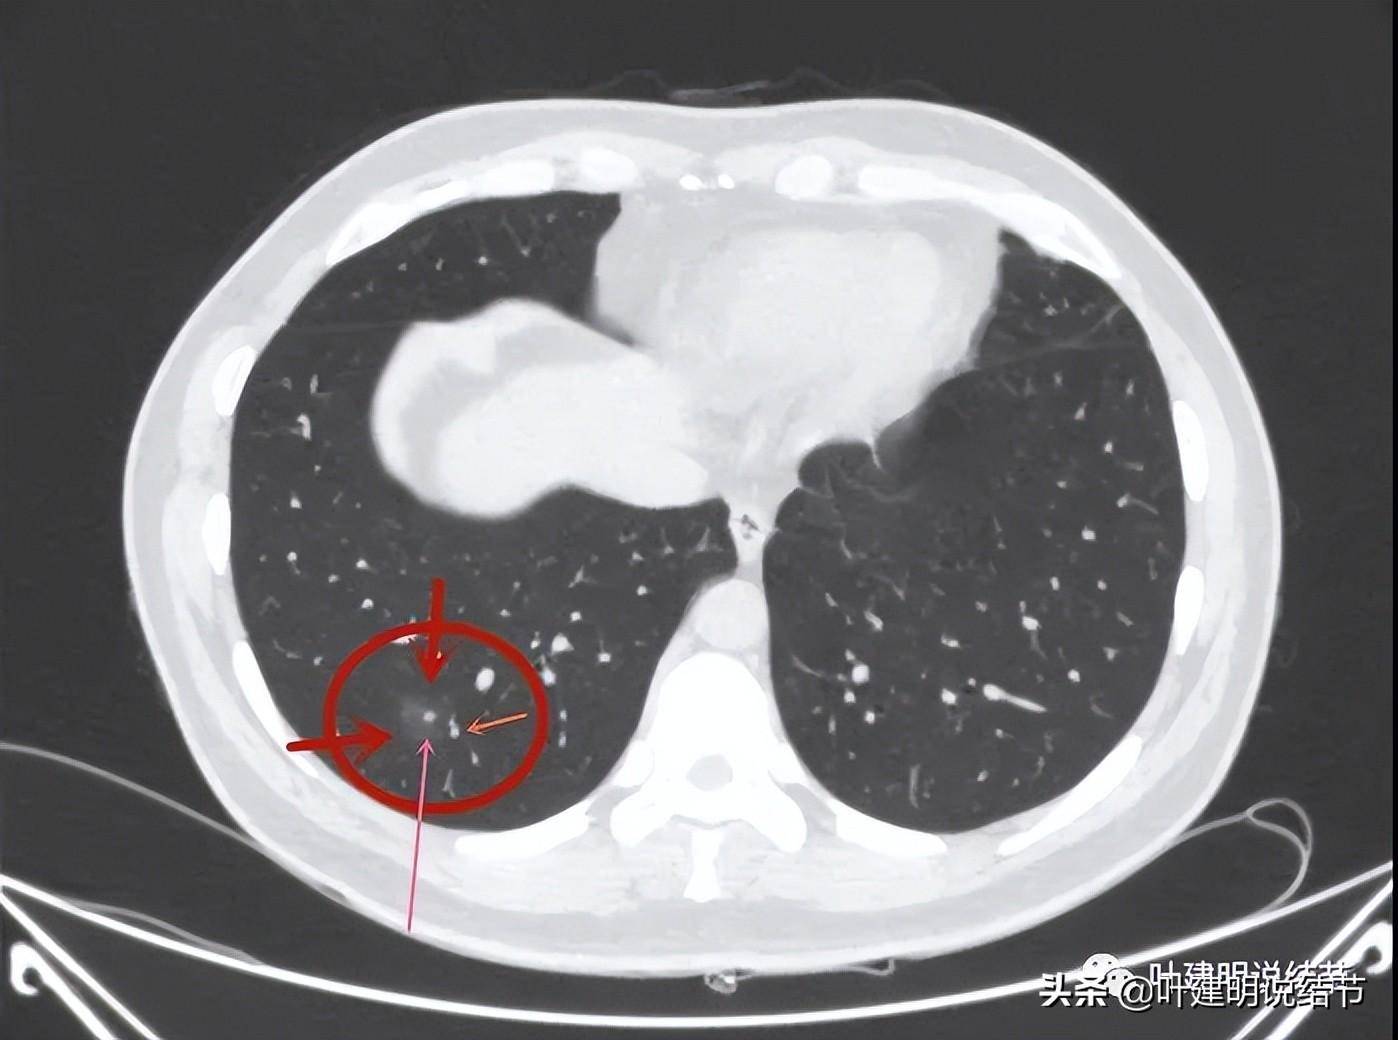

典型的右上肺腺癌的混合密度磨玻璃结节.